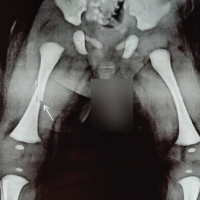

On examination, previous scar marks were visible over the hip and thigh, tenderness was present over the anterior joint line, and joint movements were restricted compared to the contralateral hip. Shortening of four cm was present over the right lower limb (Fig. 1). Radiograph of pelvis anteroposterior view revealed right dysplastic hip (Crowe’s type IV) with deformity over the shaft of the femur. Overriding of the greater trochanter and destruction of the femur head were noticed (Fig. 2). Further investigations were done, including computed tomography of the pelvis with bilateral hip and right femur for surgical planning. The patient was planned for subtrochanteric osteotomy plus THA.